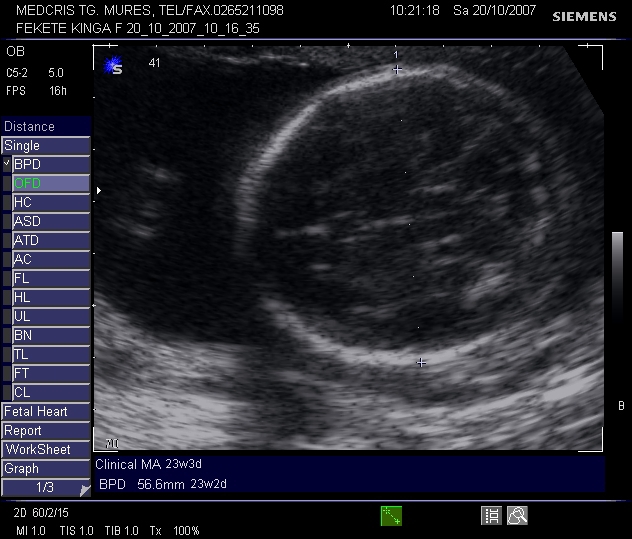

BIOMETRIA FETALA IN TRIMESTRELE II SI III DE SARCINA

Biometria fetala in trimestrele II si III de sarcina Indicatii: - urmarirea cresterii fetale normale sau discrepante inca din stadii timpurii (retardul de crestere intrauterina, maCiteste tot ... 932 cuvinte

Dimensiune mica + cu imagini |